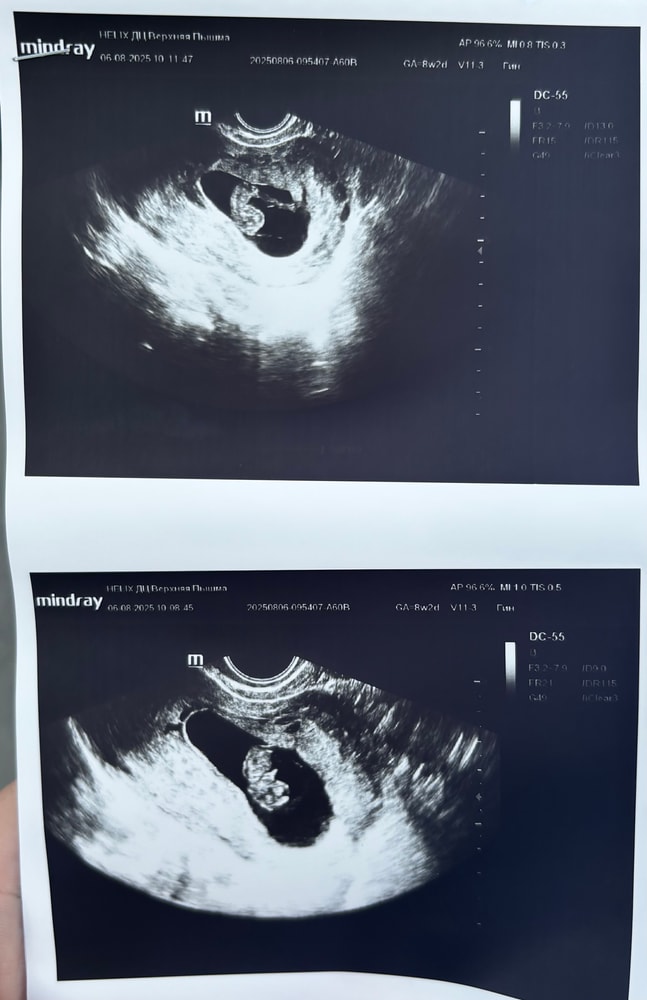

УЗИ в 9.3 недель и самочувствие

УЗИ, КТГ, доплерСходила на УЗИ, проверить малыша перед постановкой на учет. Рыб подрос, пя всё так же пентхаус по сравнению с ктр😅. После узи сдала кровь на определение пола в инвитро ждать сказали 8 дней, и наконец-то сходила в жк, встала научет. По токсикозу всё так же нету- с дочкой я умирала, сейчас повезло😃 По еде предпочтений нет, но мясо по вкусу и запаху не нравится, похудела на 4 кг с начала беременности. Расстроилась что прикрепление по передней стенке снова, видимо не судьба мне с маленьким животиком ходить 😂